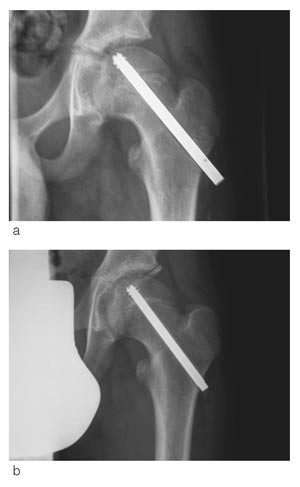

Vi fikk i 1992 spesialkonstruert en skrue som en modifisert Olmed-skrue (De Puy) og har siden da brukt denne rutinemessig ved epiphysiolysis capitis femoris. Målet var at skruen skulle kunne tillate fortsatt vekst i collum. Skruen har kortere gjengesegment enn vanlig Olmed-skrue som brukes til fractura colli femoris, for at hele gjengesegmentet kun skal stå i epifysen. Skruen er derfor glatt over vekstskiven, slik at den kan tillate fortsatt vekst i collum.

Det har tidligere vært til dels store problemer med å fjerne skruen (13, 14). For å redusere problemer med fjerning, er gjengene skjærende begge veier (fig 1, fig 2). Vi har med denne studien ønsket å kartlegge eventuelle problemer i tilknytning til operasjonsmetode både ved innsetting og ved fjerning av skruen, hvorvidt en skrue er tilstrekkelig i forhold til ev. ytterligere glidning og om det fortsatt skjer vekst i fysen. Videre har vi undersøkt forekomst av caputnekrose og kondrolyse og klinisk resultat ved oppfølging.